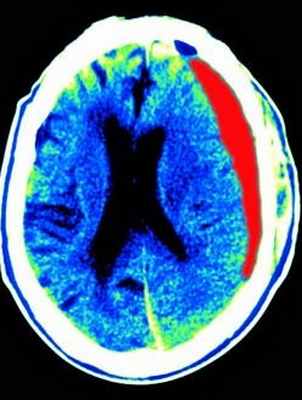

Эпидуральная гематома на КТ

Небольшое скопление крови, которое расположилось над поверхностной оболочкой мозга, называют в медицине эпидуральной гематомой. Как правило, она возникает во время перелома черепа. При таком повреждении чаще всего источником кровотечения становятся оболочечные артерии. В зависимости от расположения по отношению к мозжечку такая гематома подразделяется на подвиды:

Признаки эпидуральной гематомы на КТ

Если рассмотреть эпидуральную гематому на полученных томографических снимках, то можно отметить ее особенную форму. Она напоминает двояковыпуклую линзу, что соприкасается с костью. Иногда при переломе черепа можно наблюдать такую картину: перелом кости находится прямо в области дна гематомы.

Абсолютно точный признак эпидуральной гематомы – это наличие у углов скопления крови, так называемых, ликворных «стрелок», которые появляются в случае разрыва арахноидальной оболочки. При этом ликвор постепенно переходит из арахноидальной полости в субдуральное пространство. Тут же можно наблюдать присутствие костных отломков. Что касается строения эпидуральных гематом, то их структура по обыкновению однородная. При травмах очень редко можно встретить неоднородное скопление крови или наличие газа в черепе.

Эпидуральная гематома (экстрадуральная гематома) имеет травматическое происхождение. Это скопление крови внутренний костной пластинкой и твердой мозговой оболочкой. Обычно гематома расположена под областью перелома костей черепа. Причиной кровоизлияния является разрыв оболоченной артерии. Встречаются эпидуральные гематомы вдвое реже субдуральных. По форме гематома двояковыпуклая. Чаще всего диагностируется в неотложных условиях методом КТ. МРТ обычно применяется при спинальных эпидуральных гематомах.

КТ. Эпидуральная гематома.